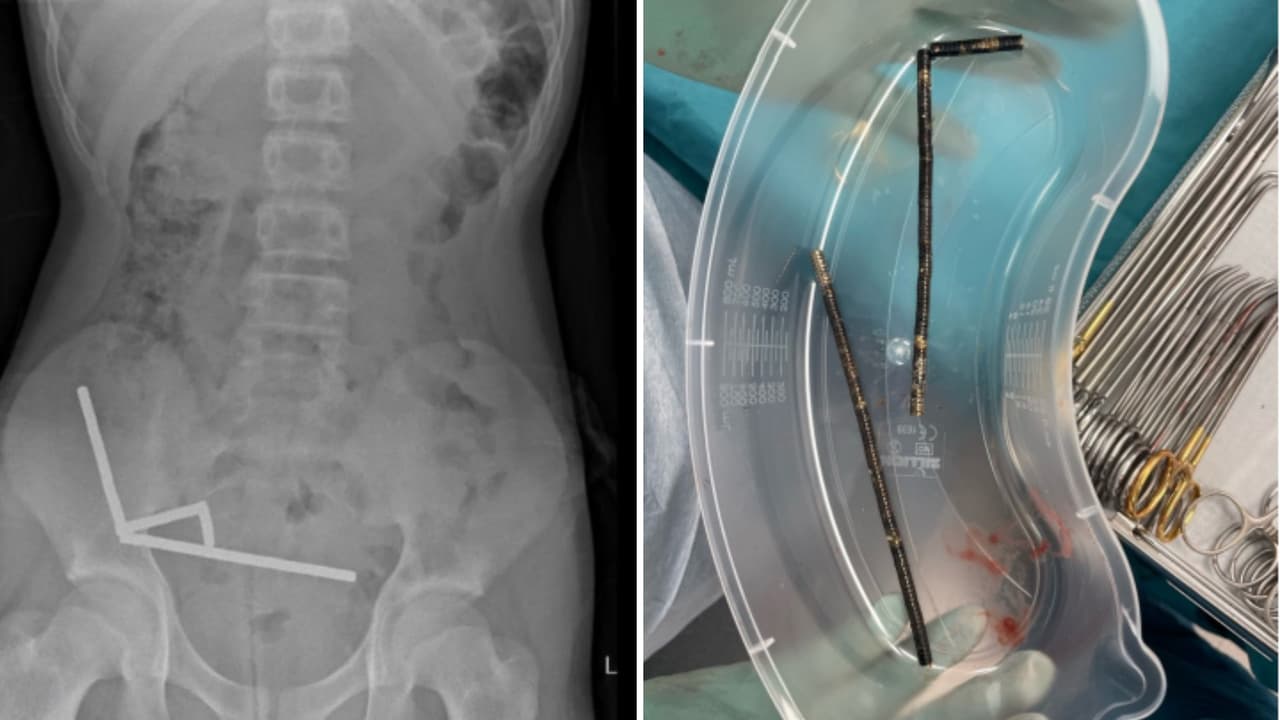

El menor que perdió parte de su intestino tras ingerir casi 100 imanes comprados en Temu

Los médicos informaron que la presión de los imanes había causado necrosis en cuatro zonas del intestino delgado, por lo que los cirujanos realizaron una operación para retirar el tejido muerto y extraer los imanes.